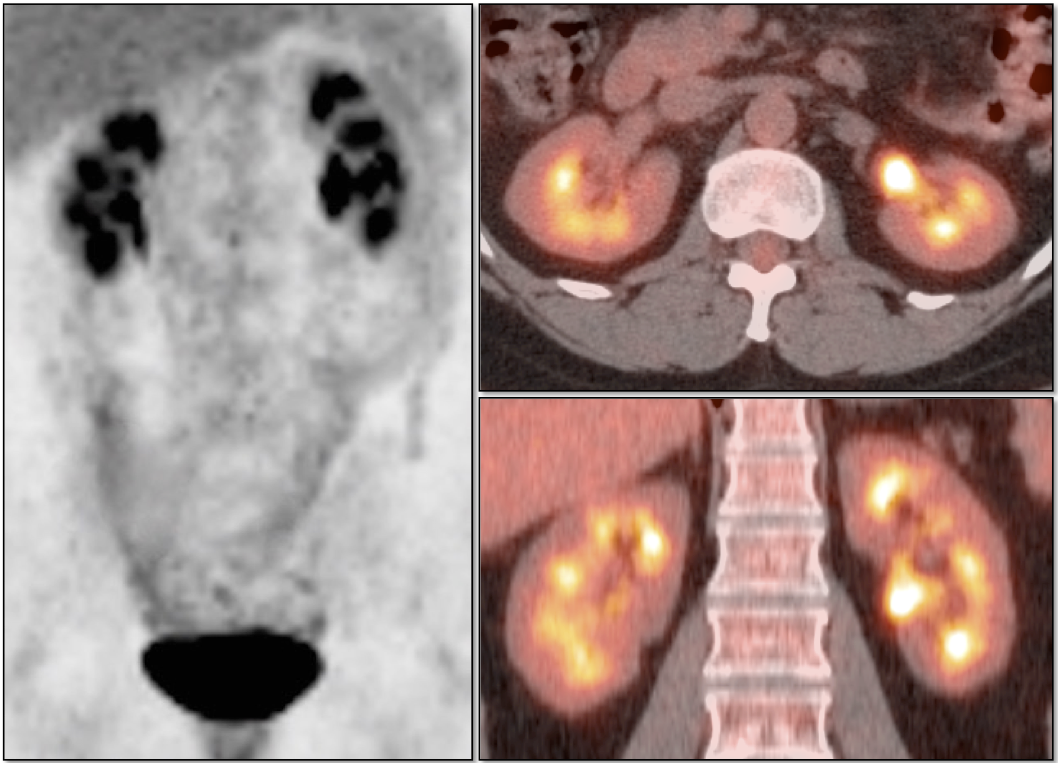

Metastatic Disease: Metastatic RCCA lesions are usually more FDG avid than the primary lesion (nearly all demonstrate metabolic activity greater than liver uptake).

• Hematogenous spread, often to lungs, bone, liver, and brain.

• Lymphatic spread to regional and distant lymph nodes.